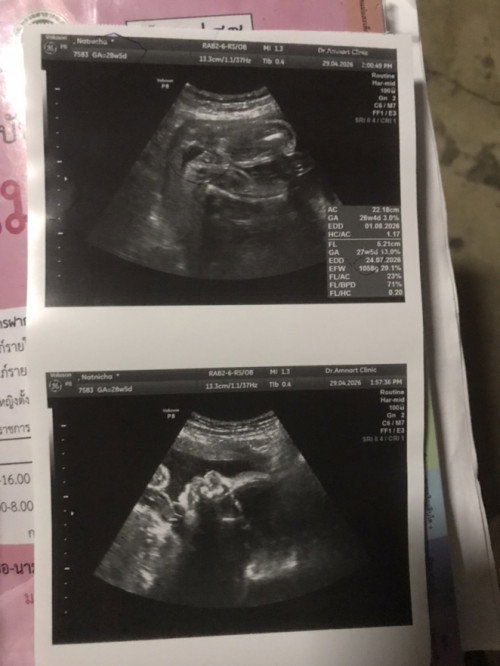

ทางนี้ได้ลูกสาวค่า ลูกคนที่สองเตรียมปิดอู่หลังคลอดแล้วค่ะ น้ำหนักจากเดือนแรก-7เดือน ขึ้นมา5โล ตรวจเจ๊เบาหวานแล้วไม่เป็น น้องดิ้นแรงมาก เริ่มท้องแข็ง1-2ครั้งต่อวันแล้ว น้ำหนักหนูตามเกณฑ์แล้วนะคะ 1,058g พี่คนโตแรกคลอด2,436gเลยมีโอกาสที่คนเล็กจะน้ำหนักน้อยตามได้พ่อสูง157แม่160 เดิมแม่เป็นซีดและตอนท้องเป็นความดันต่ำ แต่โดยรวมอยู่ในเกณฑ์ดีค่ะหายห่วงแล้วบำรุงดีมากนะคะแต่ได้เท่านี้ก็ดีใจแล้วค่ะขอให้ออกมาแข็งแรงก็พอ🤰🏻❤️👧🏻 #ขอบคณสำหรับคำตอบล่วงหน้านะคะ